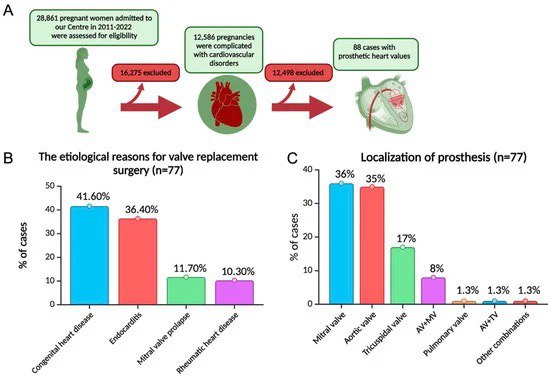

Sefiyeva G. Pregnant Woman in Outcomes with Prosthetic Heart Valves / Shadrina U., Vavilova T., Sirotkina O., Bautin A., Chynybekova A., Pozhidaeva A., Stepanovykh E., Starshinova A., Kudlay D., Irtyuga O.//Journal of Cardiovascular Development and Disease. – 2024. – Т. 11. – Vol. 11. – С. 353.

- Ведение беременных пациенток с врожденными и приобретенными пороками сердца, механическими протезами клапанов сердца, определение наиболее безопасных тактик антикоагулянтной терапии у данных пациенток.

Иртюга О.Б. является руководителем государственного задания 2023—2025 № 123021000133-8 по теме: Разработка дифференцированных подходов к выбору тактики ведения женщин репродуктивного возраста с механическими протезами клапанов сердца.

Иртюга О.Б. является руководителем гранта РФФИ 2018–2020 г. № 18-015-00016 по теме: «Патогенетическое обоснование вклада циркулирующих маркеров кальцификации в формирование аортального стеноза». Сефиева Г.Г. и Чыныбекова А.Н. являются исполнителями государственного задания 2023—2025 № 123021000133-8 по теме: Разработка дифференцированных подходов к выбору тактики ведения женщин репродуктивного возраста с механическими протезами клапанов сердца.